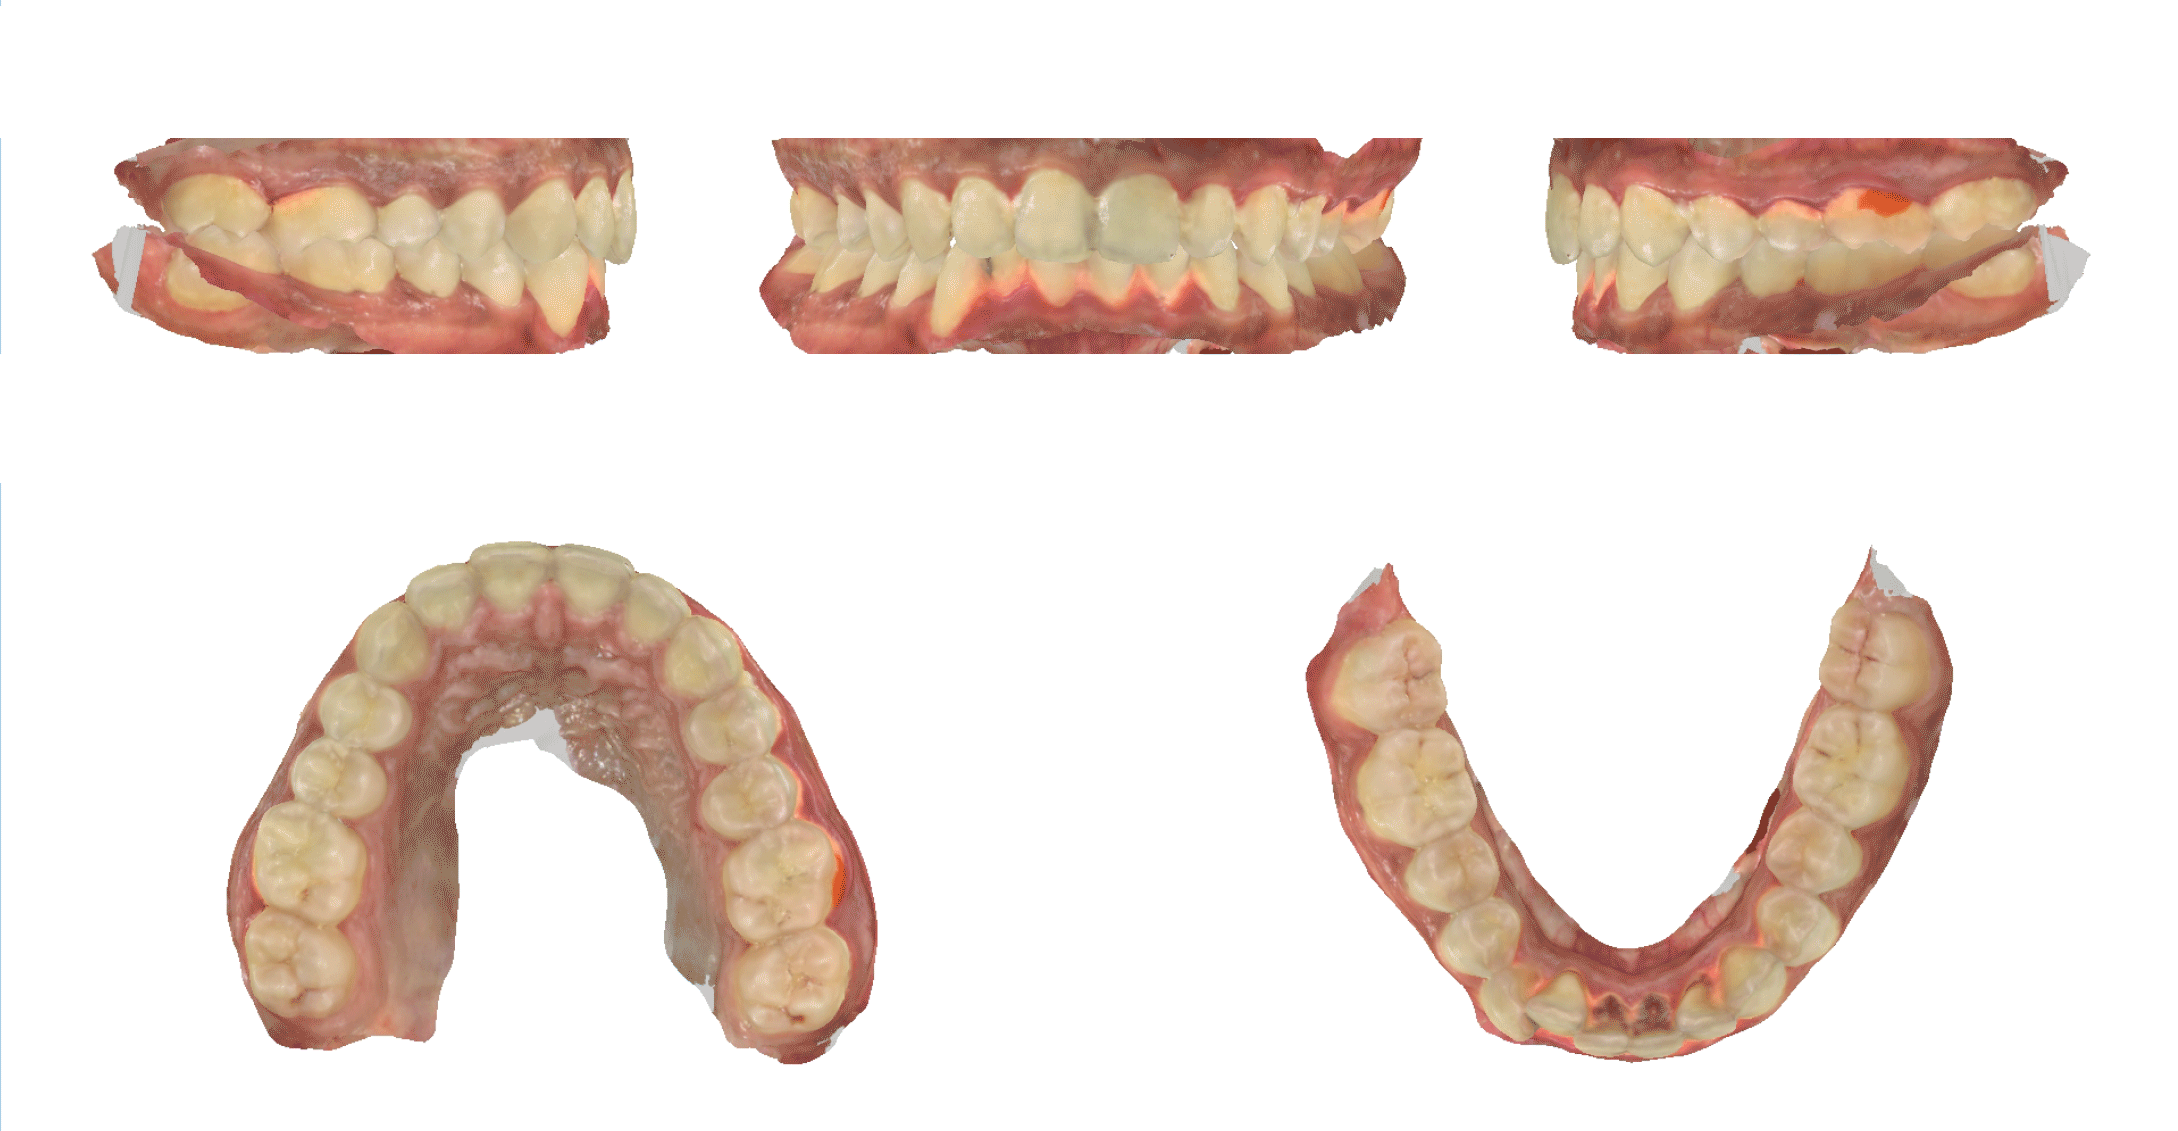

Digital Dentistry:

A Seamless Experience

Step into the future of dental care with our advanced digital dentistry solutions.

At Olive Dental, we utilize a state-of-the-art 3D intraoral scanner, replacing traditional, often uncomfortable, dental impressions.

This innovative technology creates highly accurate 3D models of your teeth and gums in minutes, enhancing diagnostic capabilities and allowing for more precise treatment planning.

From perfectly fitted crowns and veneers to streamlined orthodontic solutions, digital dentistry ensures a more efficient, comfortable, and accurate dental experience for you.